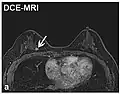

Dynamic contrast enhanced DCE Measures changes over time in the shortening of the spin–lattice relaxation (T1) induced by a gadolinium contrast bolus.[27] Faster Gd contrast uptake along with other features is suggestive of malignancy (pictured).[28]

• Dynamic contrast enhanced (DCE): Measuring shortening of the spin–lattice relaxation (T1) induced by a gadolinium contrast bolus.[46]